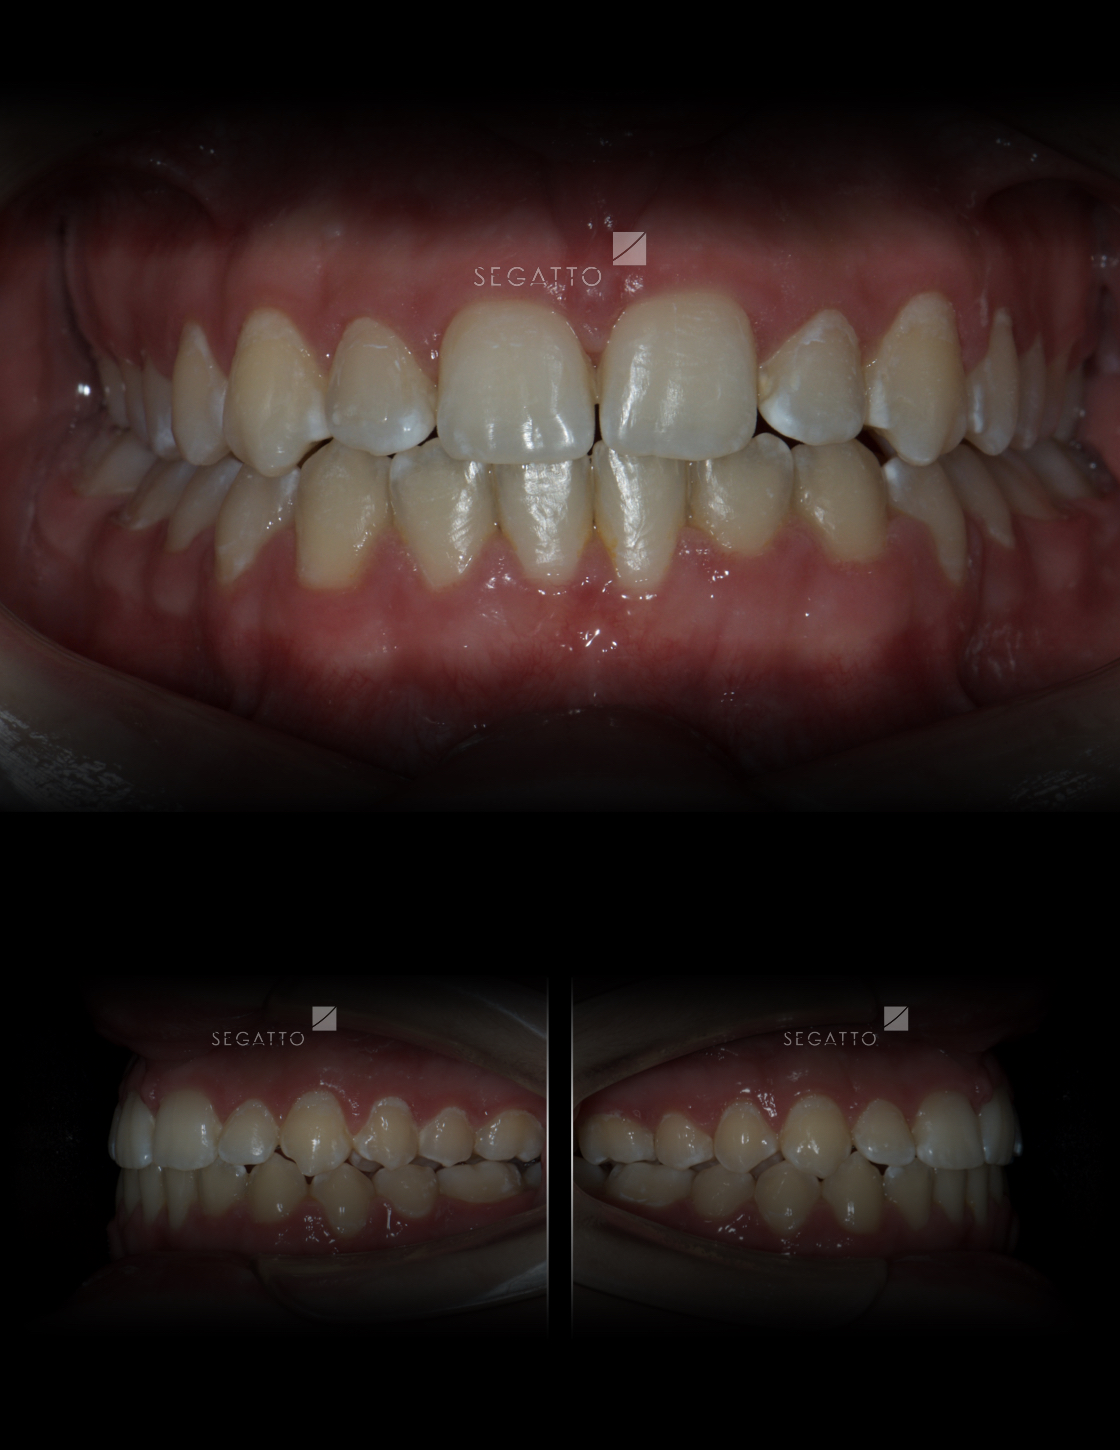

Orthodontics

Cases